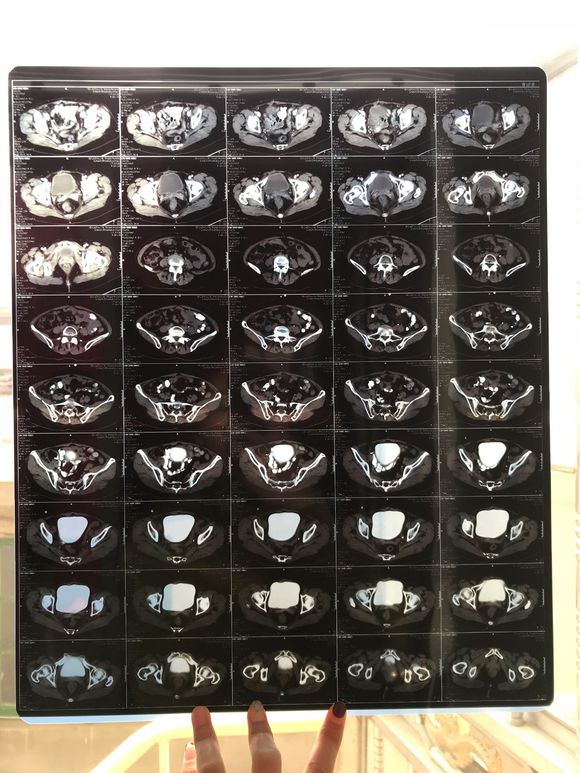

和你的故事 02019-04-09 患者家属我妈妈的病理结果报告,3期c1,大家可以帮忙看看吗,跪求了!我很急,谢谢!想知道是否严重,目前等术后出院后去肿瘤医院...

0人关注 4个回复 3509次浏览 -